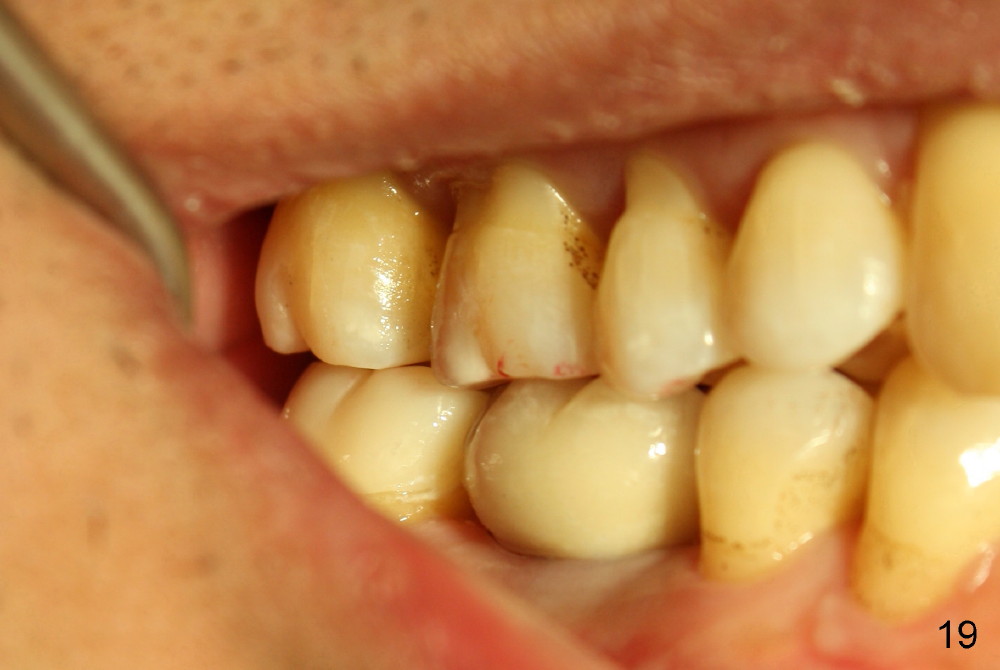

While the bone continues growing around the implant 1.5 years postop (Fig.17, as compared to Fig.12), the tooth #31 loses composite distally (*). A Zirconia onlay is cemented 1 year 10 months post implantation (Fig.18 arrowheads); the posterior interdigitation remains normal (Fig.19).